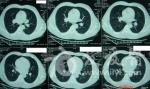

人间能得几回见:“爆米花样”钙化胸部CT

分享【一般资料】 男,44岁。 【主诉】 外伤查体发现右肺结节10天。偶有盗汗。 【辅助检查】 神经元特异性烯醇化酶偏高。 【CT表现】 右肺上叶后段斜裂胸膜及水平裂胸膜下一大一小二个(大者位于外侧)等、高混杂密度结节,内可见等密度软组织密度影及斑块状高密度钙化影,边缘规整,大结节钙化主要位于后部呈偏心性分布,前外侧肺组织内可见扇形GGO影,有胸膜凹陷征,小结节下方可见索条状影,两侧胸腔少量积液,增强大结节内等密度软组织成分有强化。 【分析思路】 中年病人,临床病人偶有盗汗,影像右肺上叶内侧较小结节病灶内有钙化,周围有卫星灶,影像高度提示为结核。右肺上叶较大结节位于叶间裂胸膜下,有胸膜凹陷征,有阻塞性肺炎,增强有强化,胸腔有积液,影像高度提示为恶性病变,所以首先想到周围型肺癌,但周围型肺癌病灶多有分叶,有毛刺,有血管集束征,实验室相关生化检查可出现异常,不太支持;结节为恶性,病人为中年男性病人,病灶属外伤查体发现,细看病灶内侧与支气管关系密切,病灶内的钙化较多,呈斑块状,呈偏心性分布,影像高度度提示为不典型类癌。1、肺不典型类癌好发于40岁以上的中老年人,临床症状无明显特异性,患者除呼吸系统症状外出现阵发性皮肤潮红、腹泻、哮喘、心悸、血压增高、满月脸等少见症状时要高度怀疑支气管肺类癌可能。2、影像学表现多为周围型单一病灶,边界清楚,分叶常见;病灶内钙化为特征表现,可以呈偏心或弥散分布,空洞少见。3、病灶较大并向周围侵犯邻近肺组织时CT可见"冰山征"表现,此征象有助于周围型肺不典型类癌的诊断。虽然确诊需要支气管镜活检和手术病理结果,但综合以上几点临床和影像学特征,仍然对肺不典型类癌的诊断提供重要的参考价值。 【CT诊断】 右肺上叶后段不典型类癌伴结核。 【鉴别诊断】 1、周围型肺癌:详见分析思路。2、肺错构瘤:CT上表现为圆形、类圆形肿块,边缘光滑,病肺交界面截然,周围的肺组织正常,典型的内钙化呈爆米花状。3、肺软骨瘤:如肿瘤较小则表现密度均匀,边缘锐利,如瘤体较大则病灶内呈不规则结节状或片状钙化灶,增强扫描无强化。肺软骨瘤多发生在下叶。肺软骨瘤可作为Carney三联征的一种征象被查出。Carney三联综合征是由肺软骨瘤、胃肠道平滑肌肉瘤和肾上腺外的功能性副交感神经瘤组成,临床上出现3种或者其中任意2种肿瘤即可诊断;该病多见于年轻女性。4、肺硬化性血管瘤:病灶肺门侧可见一尾状突起,似为尾征,故要注意与硬化性血管瘤鉴别,但本例病灶不算大,增强后应该有比较显著的强化,并可见"贴边血管征"及"肺动脉为主征",且多见于中青年女性病人。5、炎性假瘤:叶间胸膜下的病灶,与胸膜关系较密切,可呈广基相连,可有"平直征"、"向心性弓形凹陷征"及"桃尖征",病灶综含有"收缩形态"征。6、真菌感染:以继发多见,临床有引起免疫力低下的相关疾病,或有使用免疫抑制剂、激素、滥用广普抗生素等病史,影像肺内多表现为结节、纤维索条、片状与实变和空洞等多样化形式存在,实变典型的呈底部位于胸膜的楔形影,内密度均匀,边缘模糊,空洞性病灶多见,多为中心性空洞或为薄壁多房空洞,空洞内少有液平,肺曲菌病内可见曲菌球。7、肺转移瘤:病人可有原发恶性肿瘤病史,转移瘤多发多见,并且大小相差不大,边缘多较规整,转移瘤可有胸膜凹陷征,但无阻塞性肺炎表现,两肺门和/或纵隔可见有肿大淋巴结。先看病史及辅助检查如图